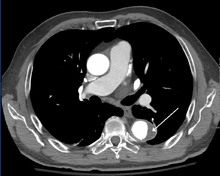

Computed tomography

CT with contrast demonstrating aneurysmal dilation and a dissection of the ascending aorta (type A Stanford)

Chest CT with descending (type B Stanford) aortic dissection (red circle)